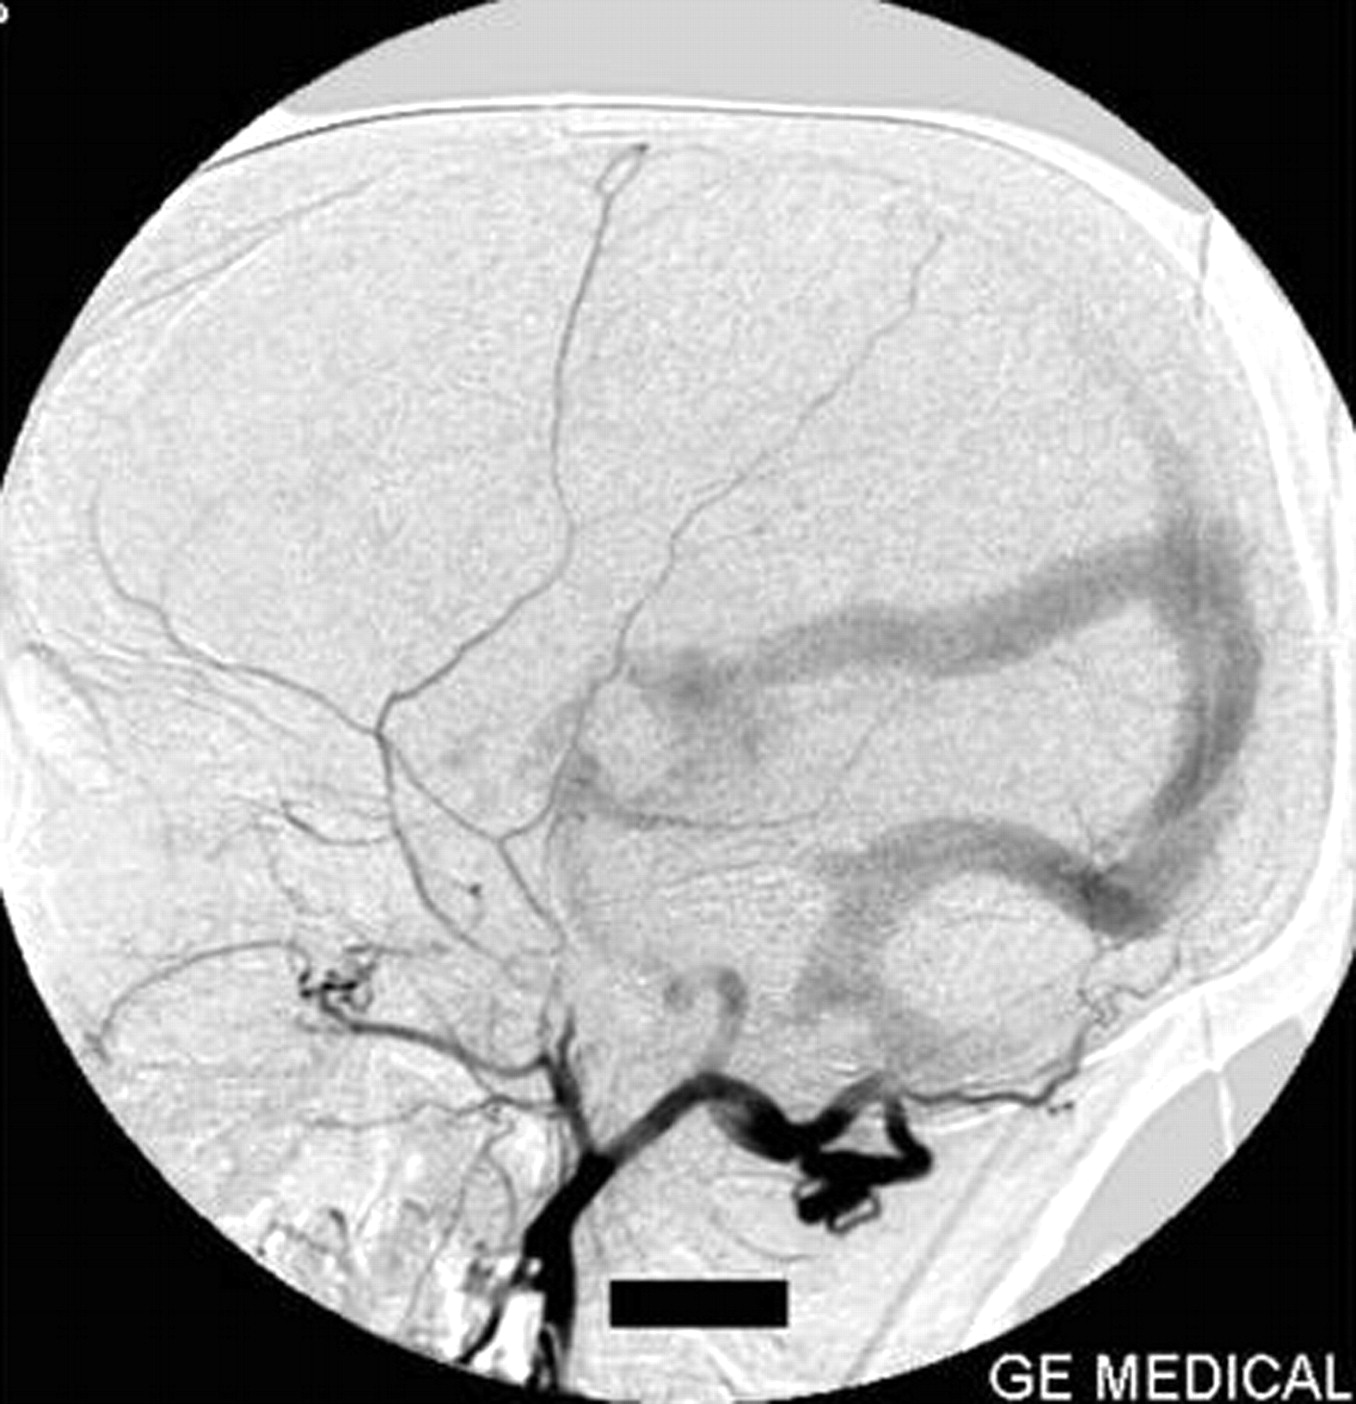

A Galen’s vein fistula was fed by thalamoperforating arteries, medial posterior choroidal arteries, and quadrigeminal arteries from both the right and left sides (Fig 2). The right perisplenial branch of the anterior cerebral artery and a branch of the left distal middle cerebral artery were also supplying the fistula (Fig 3). Bilateral posterior communicating arteries were enlarged to supply the fistula from the carotid arteries (Figs 2, 4). The superior sagittal sinus was not opacified from anterior circulation. Both middle cerebral and anterior cerebral arteries were draining via enlarged superficial cortical veins to the cavernous sinus and then via superior and inferior ophthalmic veins and the pterygoid plexus of veins. Engorged veins were seen in the falcine and tentorial leaves.

Right vertebral artery injection lateral view angiogram shows filling of the Galen’s vein fistula and the falcine sinus.